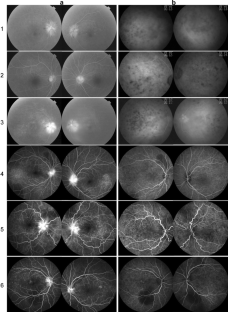

The patients with associated visual field loss were four males and two females between 54 to 79 years of age. They had bilateral panuveitis associated with meningismus. All of the patients had bilateral optic disc swelling and fluorescein angiography showed both a filling delay and late leakage of the optic disc. Visual field examinations revealed various degrees of visual field defects in 11 eyes. They were treated with high-dose corticosteroid therapy, and several weeks later, both the uveal inflammation and optic disc swelling disappeared. The visual fields showed some improvement as the retinal detachments and disc swelling resolved, but the visual field defects remained in ten eyes. The small and localized visual field defects were asymptomatic. Subsequently, optic disc pallor developed in nine eyes and retinal nerve fiber layer thickness, measured by optical coherence tomography, was decreased in six eyes. The fundus gradually showed various degrees of hypopigmentation, but did not show any chorioretinal atrophy causing visual field loss. Four patients had risk factors for AION, including diabetes mellitus or a relatively small optic nerve head.

Fig. 1

Fig. 2

Fig. 3